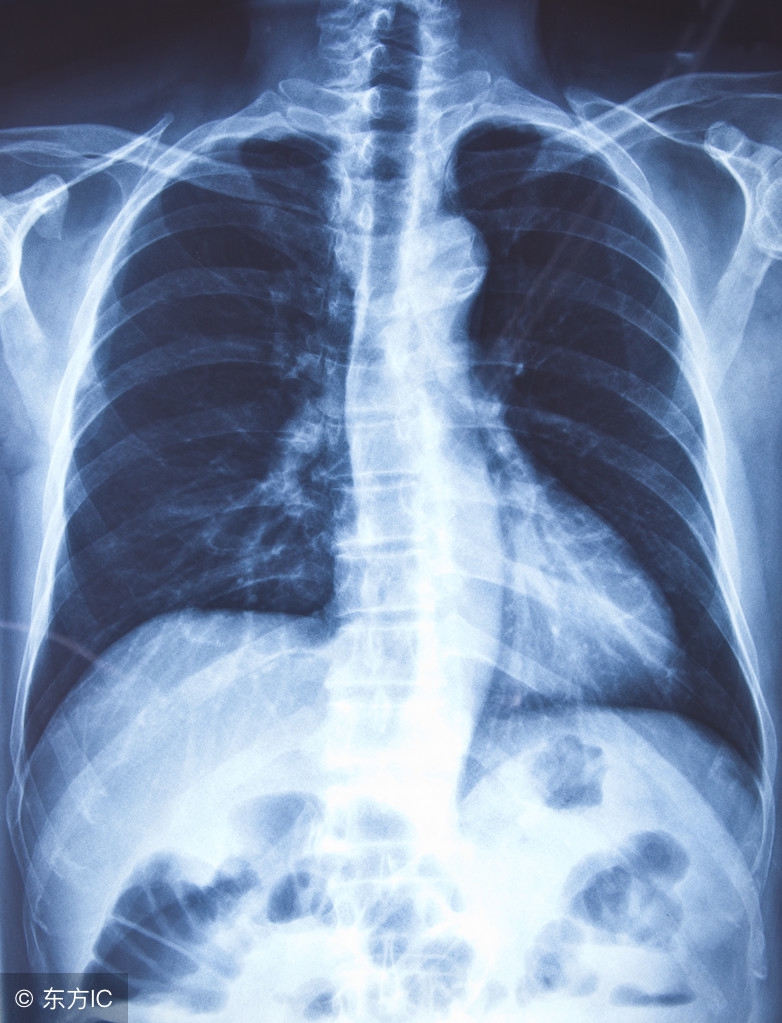

支气管炎是支气管的炎症性疾病,通常由于感染所致。患病率高,一年四季均可发生,冬春季节达高峰。临床上以长期咳嗽、咳痰或伴有喘息及反复发作为特征。如果症状持续存在,则需进行胸部X线检查,以确定是否合并肺炎。